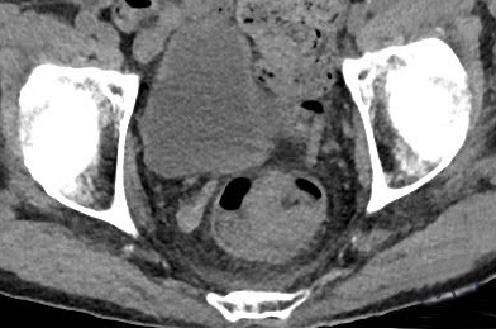

• 计算机体层摄影血管造影在腹腔镜结肠癌根治术前评估中的应用效果

摘要:目的 分析计算机体层摄影血管造影(CTA)在腹腔镜结肠癌根治术前评估中的应用效果。方法 回顾性分析2021年1月-2024年2月于该院接受腹腔镜结肠癌根治术的120例患者的临床资料。其中,60例行常规腹部CT和CTA,60例行磁共振成像(MRI)。以术后病理为金标准,判断CTA对临床T分期与术后病理的一致性,以及评估肿瘤是否侵犯肠系膜血管和周围组织的准确度。结果 术前CTA诊断T分期的准确率为95.00%(57/60),一致性好(Kappa = 0.925,P < 0.05);术前MRI诊断结肠癌T分期的准确率为98.33%(59/60),两者比较,差异无统计学意义(χ2 = 0.26,P > 0.05)。CTA预判肿瘤是否累及肠系膜上动脉、肠系膜上静脉、肠系膜下动脉、肠系膜下静脉、腹主动脉、肾动脉、肾静脉和脾动脉等血管,与术后病理的一致性好。特别是在预测肠系膜血管受累方面,CTA的敏感度为94.44%,特异度为95.83%,准确度高达95.00%。结论 对于行腹腔镜结肠癌根治术的患者,术前CTA不仅能清晰地显示结肠癌T分期,还能揭示肠系膜血管的走行和变异,以及肿瘤与周围组织的关系和侵犯程度,从而为手术规划提供强有力的支持,确保了腹腔镜手术的安全性,减少了不必要的手术风险。